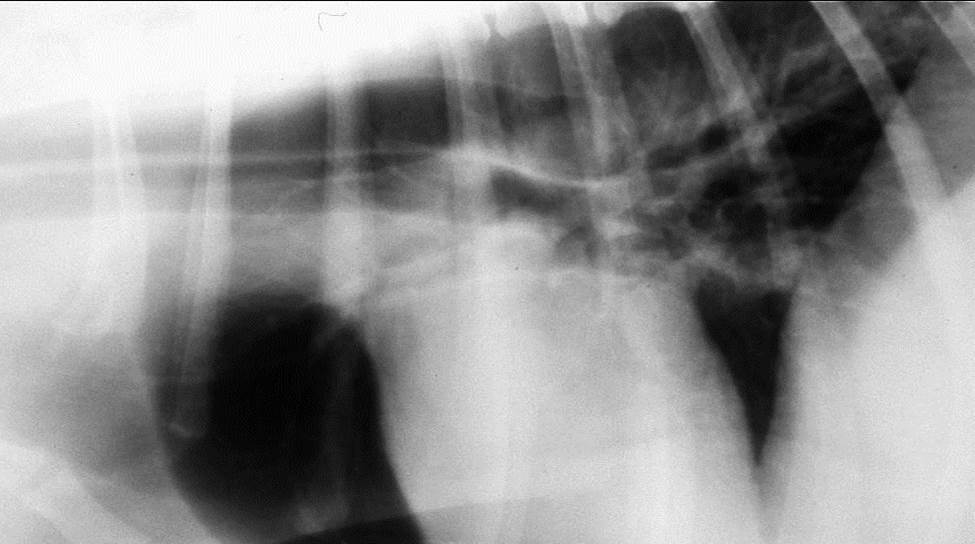

What can be seen here?

Cranial mediastinum

Midline, homogenous soft band

Shouldn’t be any wider than twice the width of thoracic vertebrae